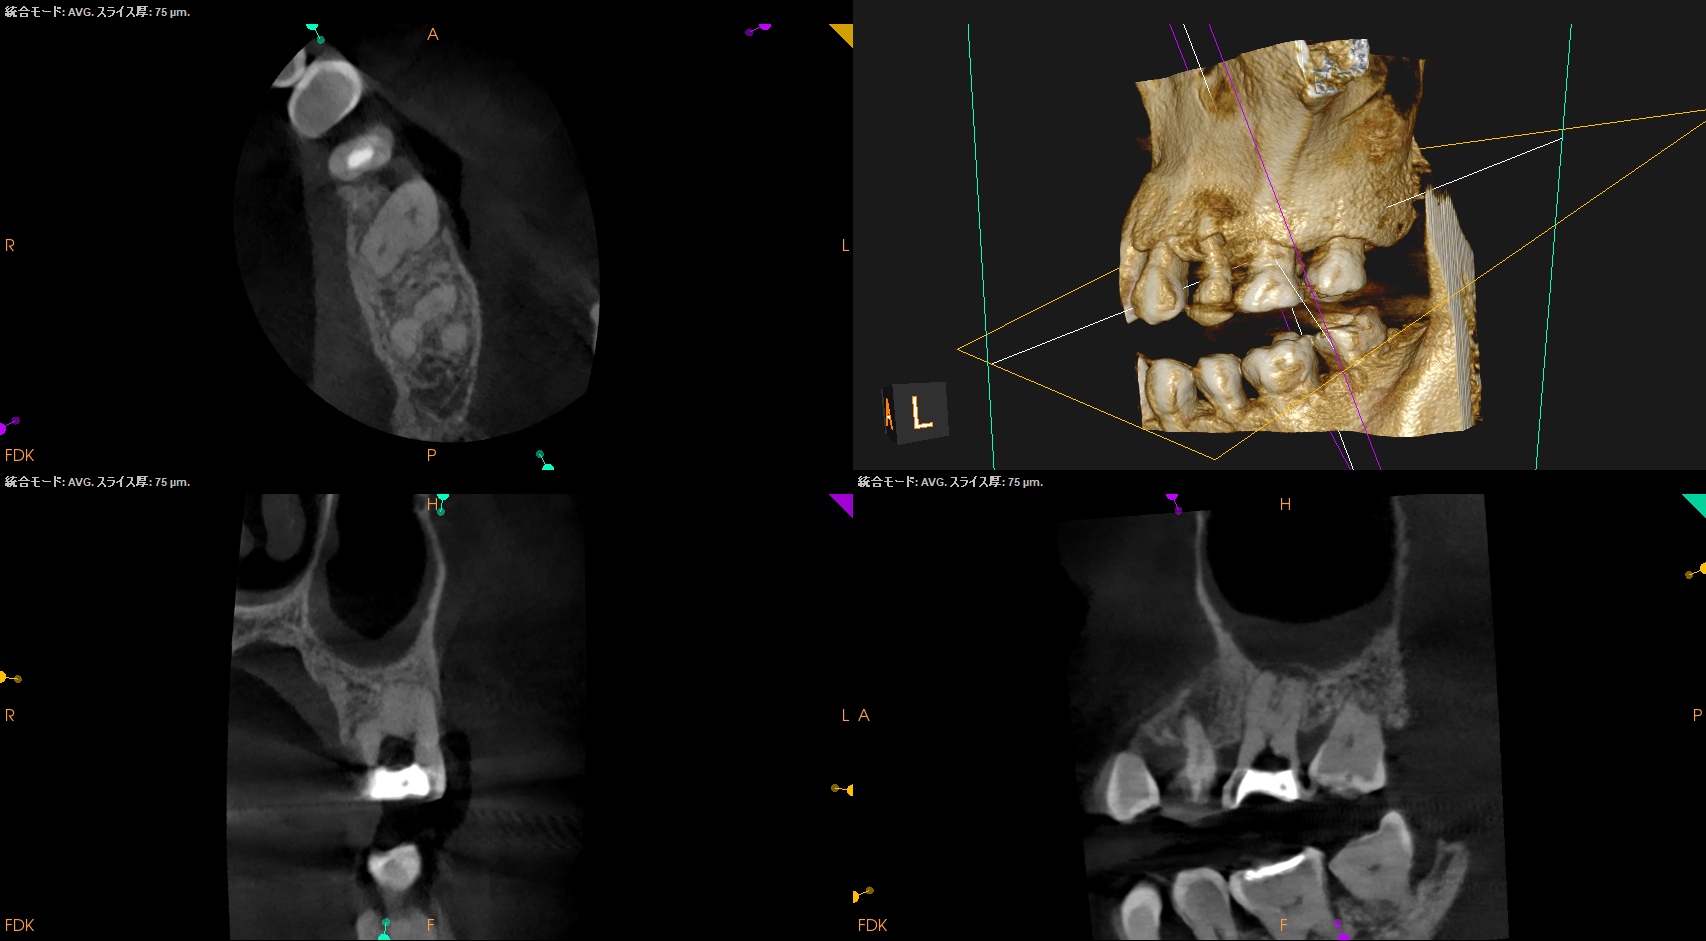

CBCTも撮影した。

これはマストの医療行為である、と私からは告げておこう。

その理由もBasic Course 2026で扱います。

が、いずれにしてもこの治療での最大のポイントになるのはMB2がどこにあるか?である。

MB2の根尖部にはCBCTで根尖病変があるからだ。

さて皆さんは気が付いただろうか?

作業長が術前に予測したCBCTでの作業長に近似していること

を。

これが、

CBCTの威力

である。